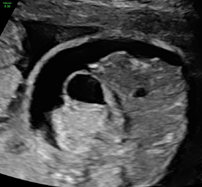

胎兒超音波 - 肝臟鈣化點

今天下午的高層次超音波中,有一位是意外發現肝臟鈣化點,除此之外胎兒的結構都正常。

中間有黃色量測的白點就是肝臟的鈣化點。雖然說單純的鈣化點意義不明,但是幾篇文獻都指出,排除了染色體和先天性感染的問題之後,單純的肝臟鈣化點基本上不會造成寶寶生理上的問題,出生後預後也很好。